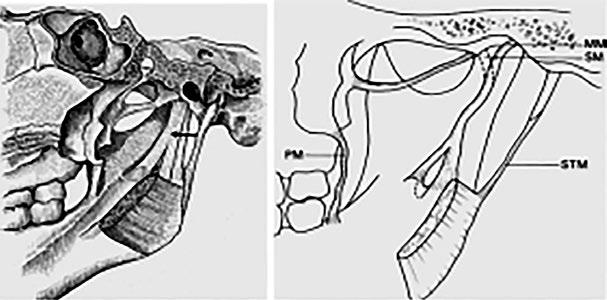

Obr. 1.14 Ligamentum sphenomandibulare – srovnání klasického anatomického schématu (vlevo – označeno šipkou) a skutečného stavu (vpravo)

SM ligamentum sphenomandibulare, část upínající se na spina ossis sphenoidalis

MM ligamentum sphenomandibulare, část pokračující do středoušní dutiny

PM raphe pterygomandibularis

STM ligamentum stylomandibulare (modifikováno podle Cheynet et al., 2003)